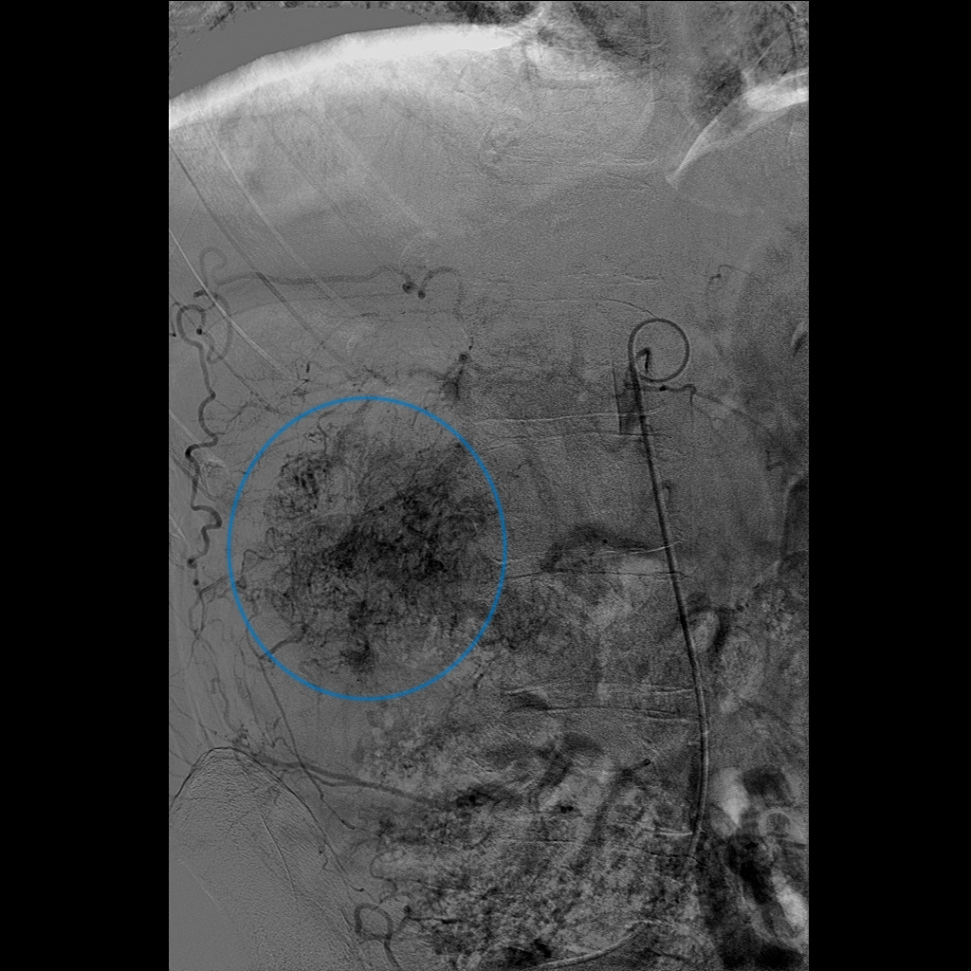

Inden for den blå ring ses tumorkar til en nyretumor.